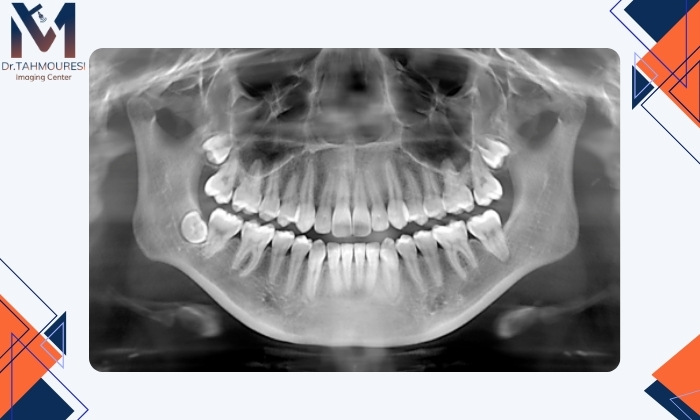

در حالت عادی استخوان اطراف ریشه دندان در این تصاویر بهصورت ناحیهای متراکم و یکنواخت دیده میشود. اما زمانی که عفونت ایجاد میشود، بهویژه در ناحیه ریشه یا انتهای کانال دندانی، در تصویر رادیوگرافی ممکن است تغییراتی مشاهده شود.